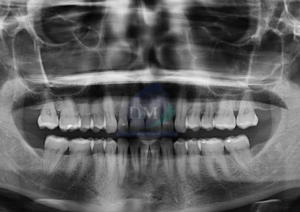

Paciente femenino de 16 años acude al Instituto de Diagnóstico Maxilofacial (sede Miraflores) para evaluación quirúrgica. Radiografia Panorámica A la evaluación de la radiografía panorámica